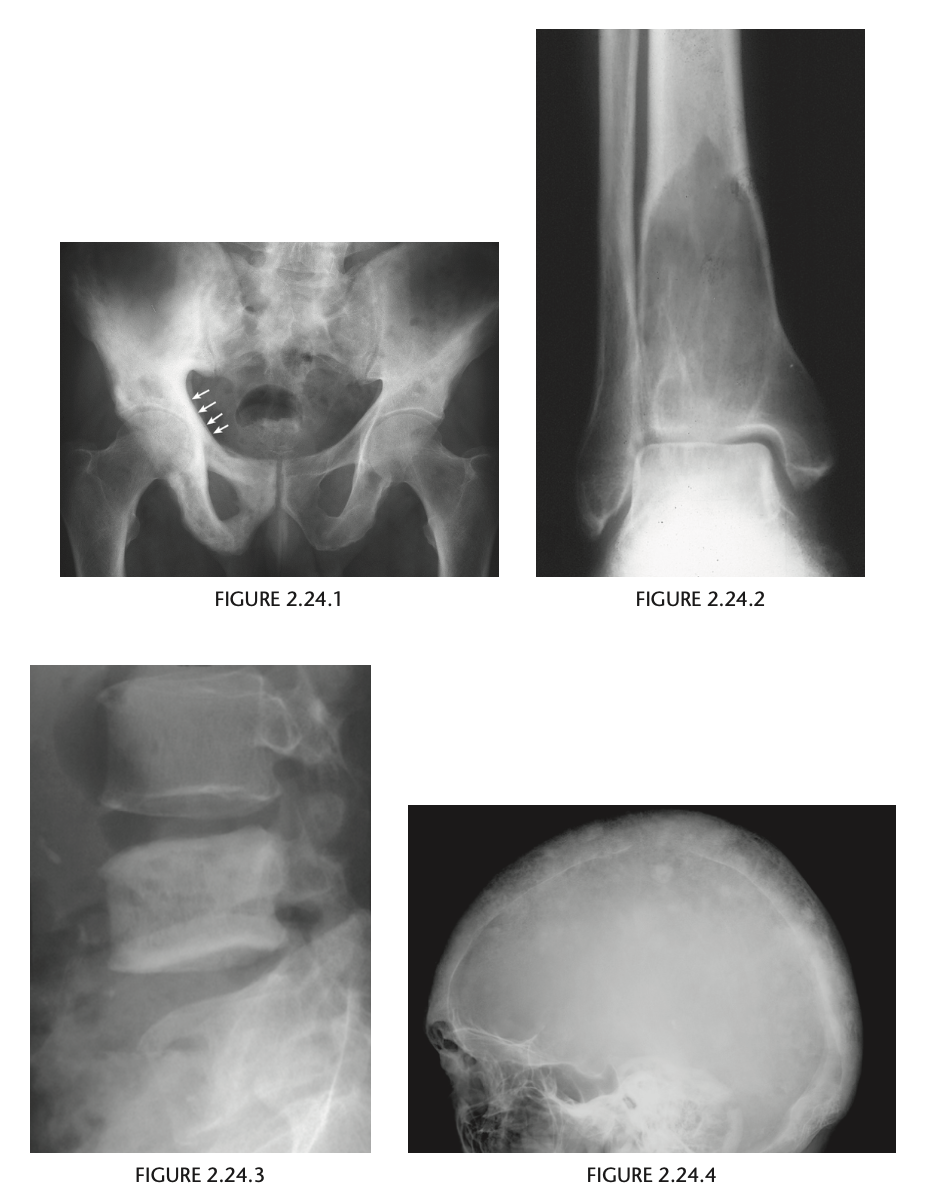

23

An anteroposterior view of the pelvis

(Fig. 2.24.1) in an elderly man shows extensive thick-

ening of the right iliopectineal line (arrows) with

coarsening of the trabecular pattern and increased

sclerosis throughout the entire right hemipelvis.

Paget disease (i.e., osteitis deformans)

disordered bone

remodeling affecting osteoblastic and osteoclastic

activity. Osseous involvement may be monostotic

or polyostotic, and 80% of the patients are asymp-

tomatic at the time of the discovery of the disease,

usually as an incidental finding on radiography or

because of elevated serum alkaline phosphatase and

elevated serum and urinary hydroxyproline.

stage I (acute phase), active and unbalanced osteo-

clastic bone resorption usually causes areas of lytic

bone destruction. In stage II (intermediate phase),

increased osteoblastic activity results in thickening of the cortex, coarsening of the trabecular pattern,

generalized bone overgrowth, and loss of corticome-

dullary differentiation. In stage III (late or inactive

phase), there is a diffuse increase in the density of

involved bone. Stage IV is the superimposed malig-

nant degeneration of Paget disease into a osteosarcoma.

radiographic findings in the acute phase are

osteoporosis circumscripta, in which an advancing

lytic area is seen in the frontal or occipital regions of

the skull, and subarticular osteolysis in the diaphy-

ses of the tubular bones, especially the tibia, yield-

ing a flame-shaped or “blade-of-grass” appearance

(Fig. 2.24.2). In the intermediate stage, there may

be bowing of the long bones, an “ivory” or “pic-

ture frame” vertebral body (Fig. 2.24.3), and more

extensive calvarial osteosclerosis superimposed on

a background of osteolysis, resulting in the cotton-

wool appearance of the skull.

In the long bones of the lower extremity, corti-

cal thickening, increased trabecular coarseness, and

bowing can be seen (Fig. 2.24.5), and CT can confirm

these findings (Fig. 2.24.6).

MRI can be used to detect malignant sarcomatous de-

generation by showing new bone destruction, soft-

tissue masses, and bone and soft-tissue edema.